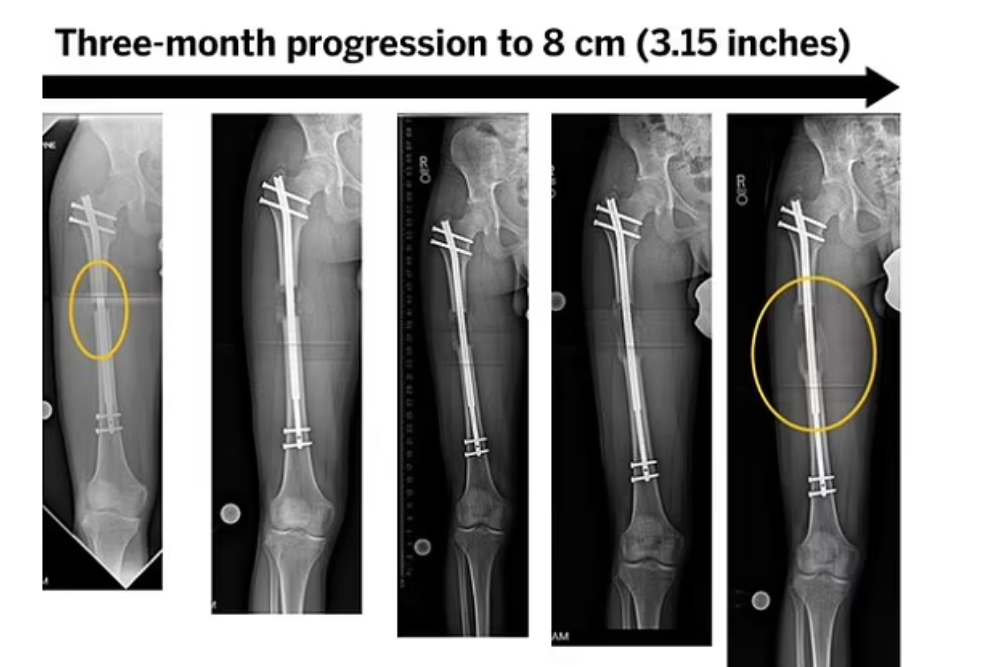

29歲男網紅科西奧(Yeferson Cossio)本身已有5呎8吋高,他說因有不方便說明的腳患問題,而決定在首都波哥大(Bogota)一診所做斷骨增高手術。手術涉及把其腿骨斷開,再加上金屬磁力支架,之後再用遙控方式將支架逐少伸長,拉長腿骨及肌肉組織。目前Cossio已接受手術4個月,據報每天可以增高約1毫米,若一切順利,他最終可以增高4吋。